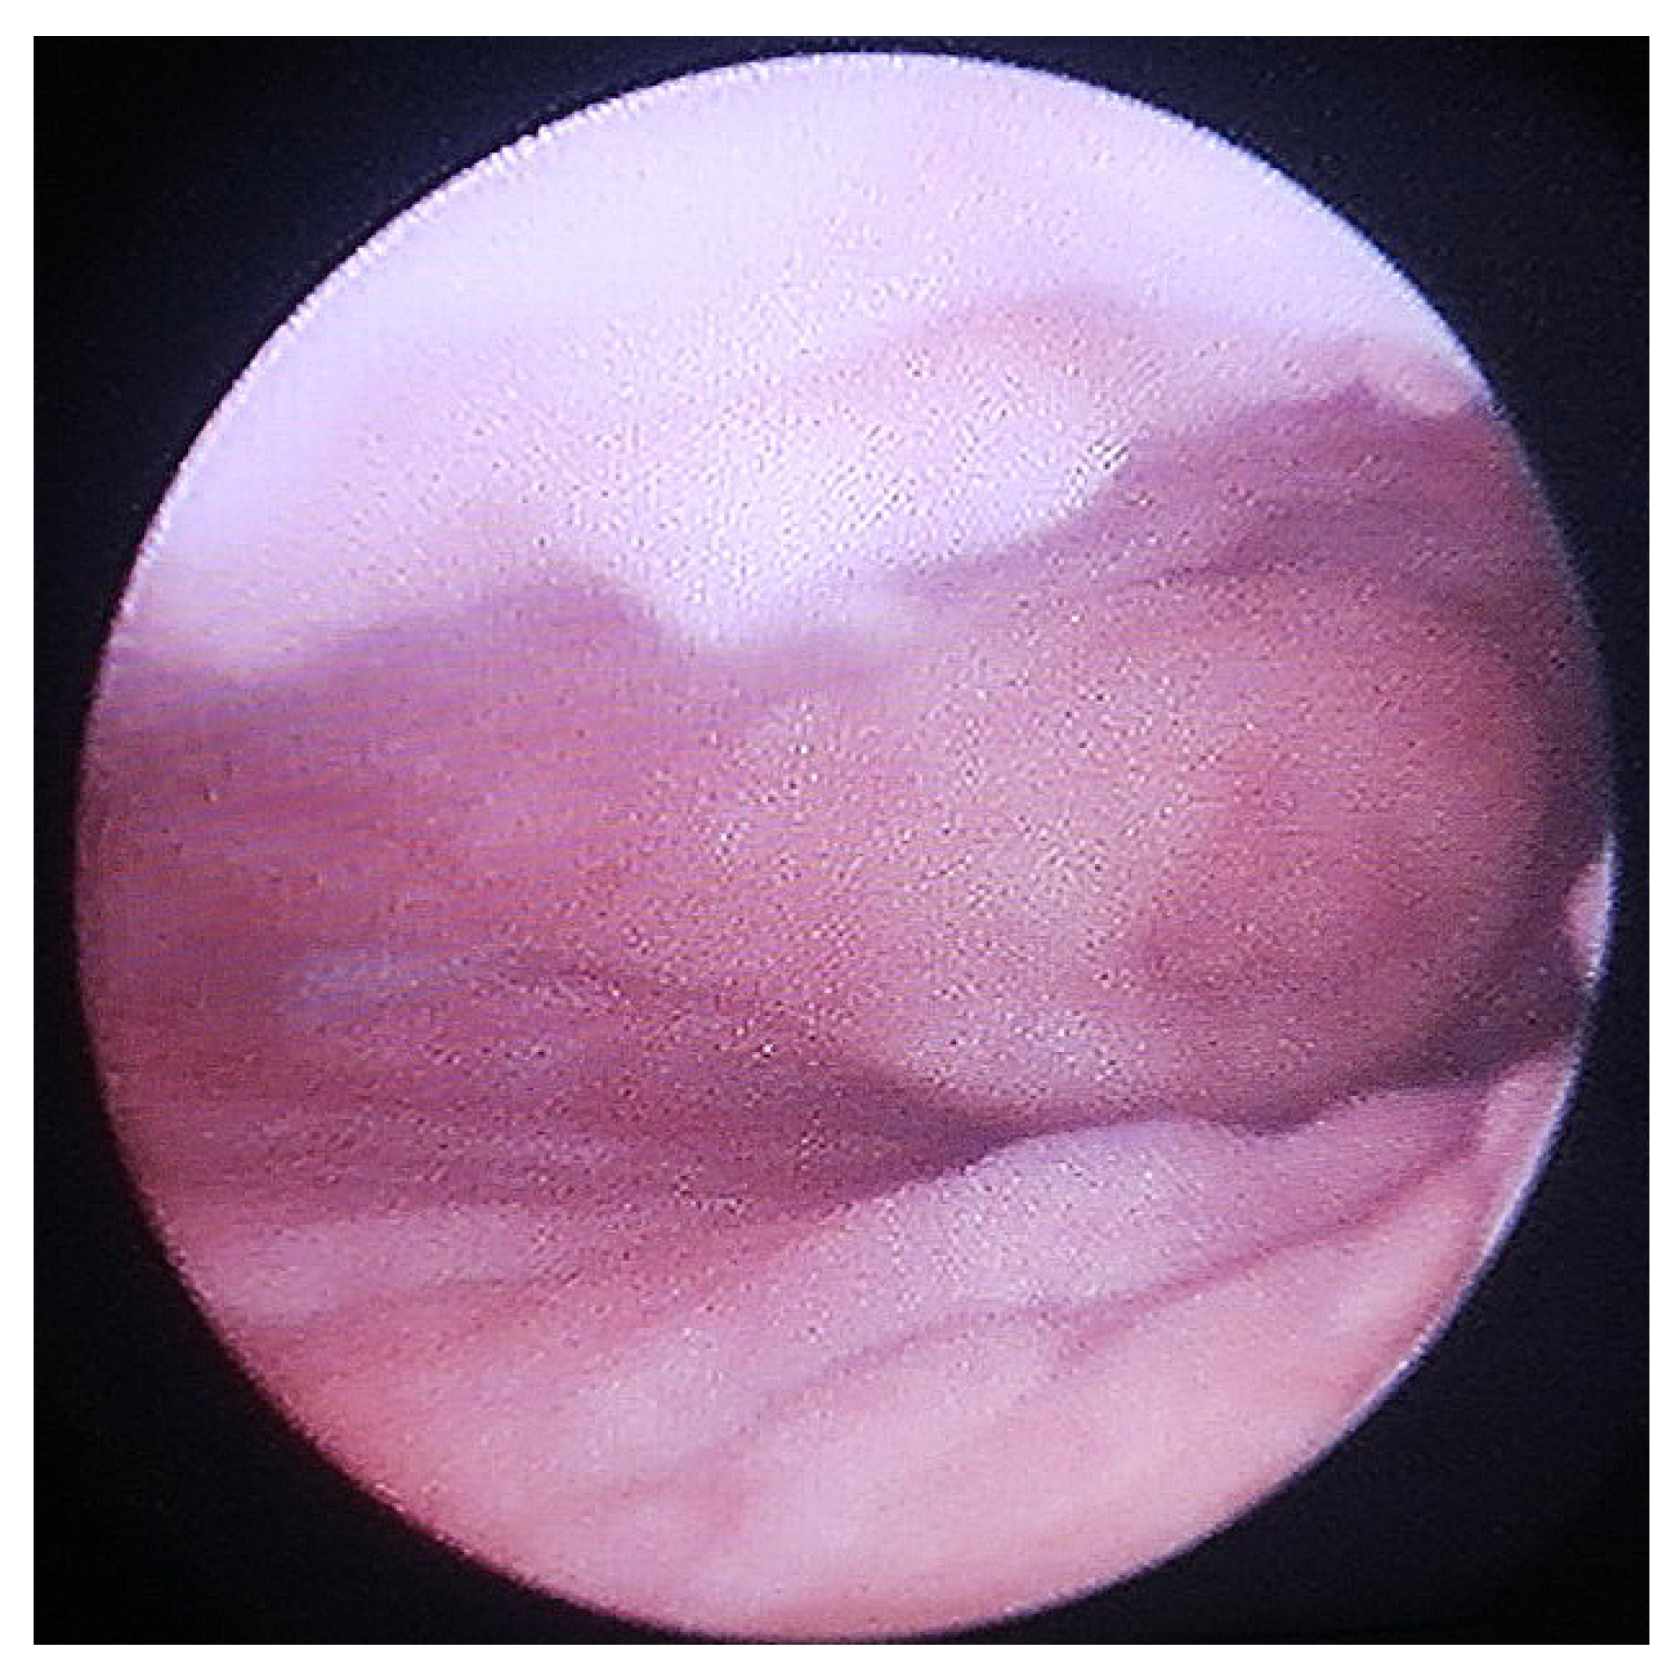

2. Materials and Methods

2.1. Approach

2.7. Vaginal Injury

2.8. Complete Urethral Loss